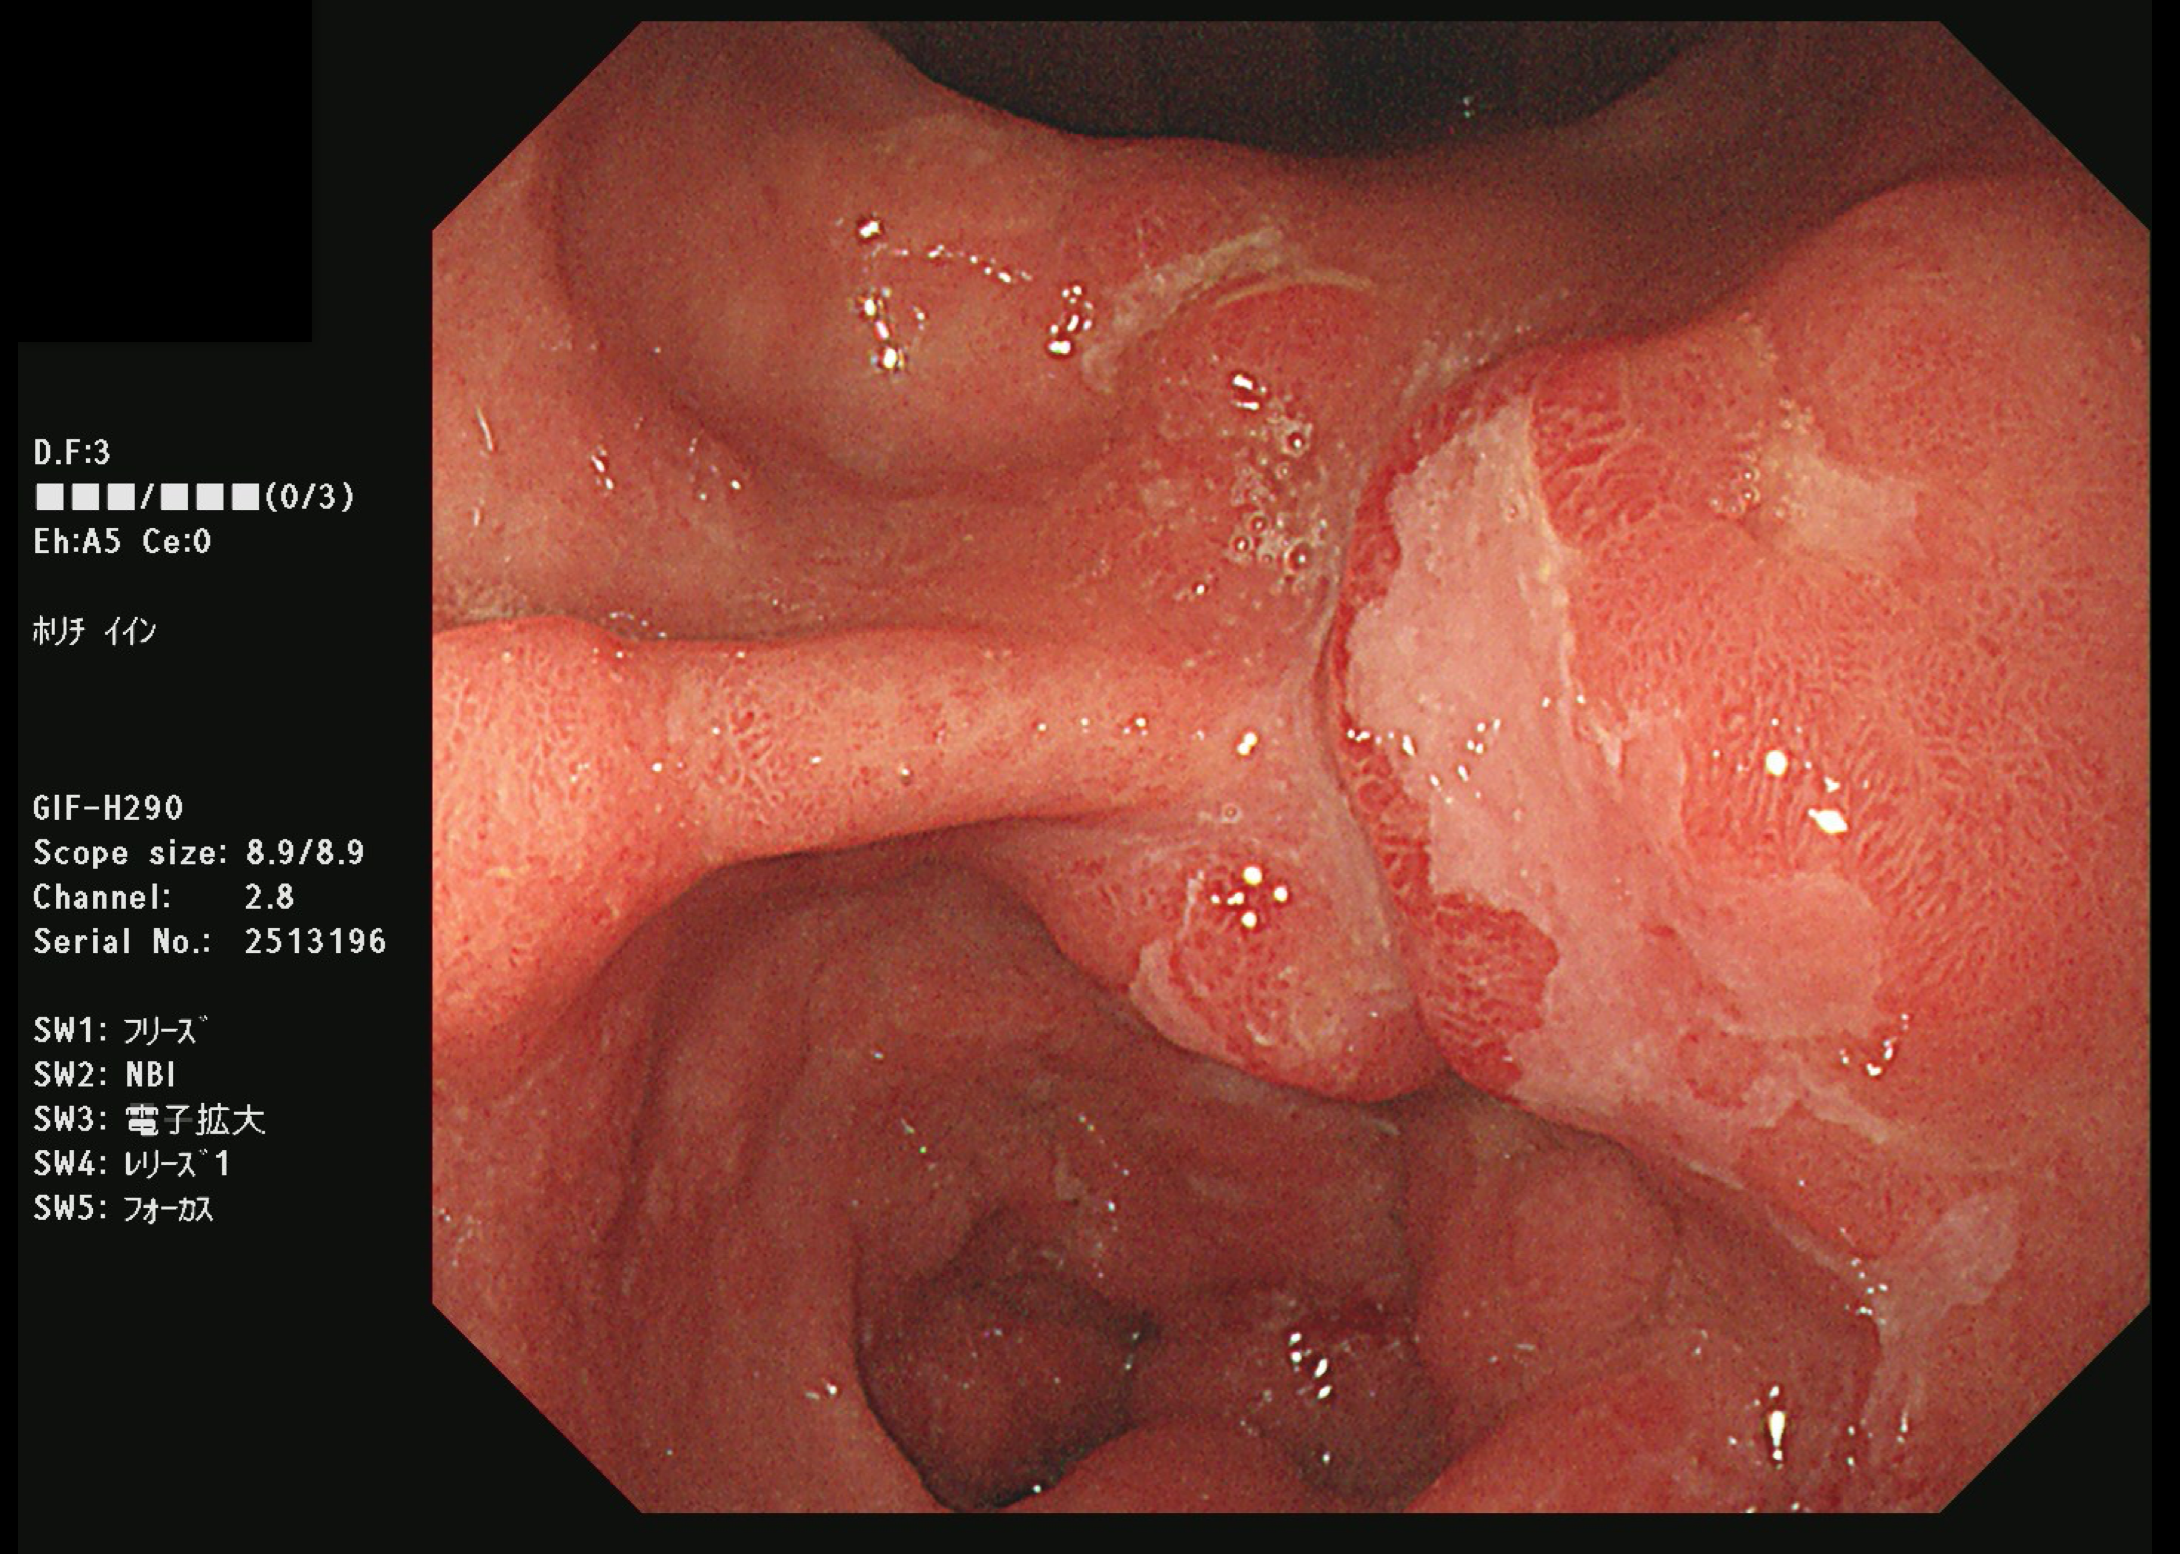

食道がん(上部消化管内視鏡)

胃がん検診では喉頭部・食道・十二指腸上部を観察します。

当院では胃内視鏡(経口)のみを実施しております。胃の中を十分に検査するために高解像度の内視鏡を使用しており、そのため口からの内視鏡検査となります。一般的に鼻からの経鼻内視鏡による検査の方が楽な検査と言われていますが、内視鏡が細い分、最新型の経口高解像度内視鏡に比べて解像度が落ちます。